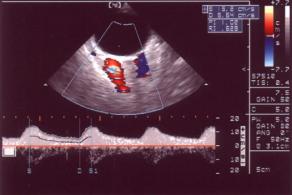

1、螢光素眼底血管造影(FFA)造影早期,腫瘤處以無螢光為主要表現,少數病例在無螢光的背景下出現迂曲盤鏇的異常血管形態。動靜脈期有的腫瘤血管與視網膜血管同時顯現,呈雙循環現象。隨螢光造影時間延長,多數病例出現高螢光亮點及毛細血管擴張。造影晚期呈現高低螢光混雜鶒的斑駁狀螢光,染料向外擴散,有的在腫瘤外圍形成一高螢光暈或高螢光弧。

2、脈絡膜血管造影也稱吲哚青綠血管造影(ICGA)。脈絡膜黑色素瘤的ICGA可有多種螢光表現。在它的生長過程中,因為毒素、壞死、機械性推擠對其周圍組織可造成損害,也影響血管通透性;瘤體的色素、厚度內在血管的多少和滲漏的程度都可影響它的螢光強弱。如將血管和色素兩種因素相比較,前者更為重要,血管多而色素少的腫物螢光顯強,反之顯弱厚的腫物常有大口徑血管存在,螢光可偏強。